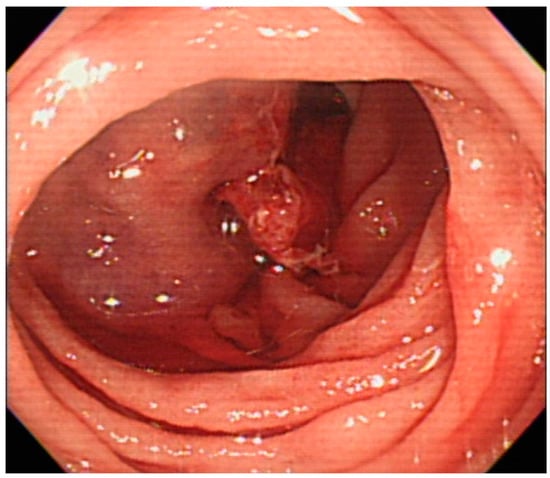

2. Case Report